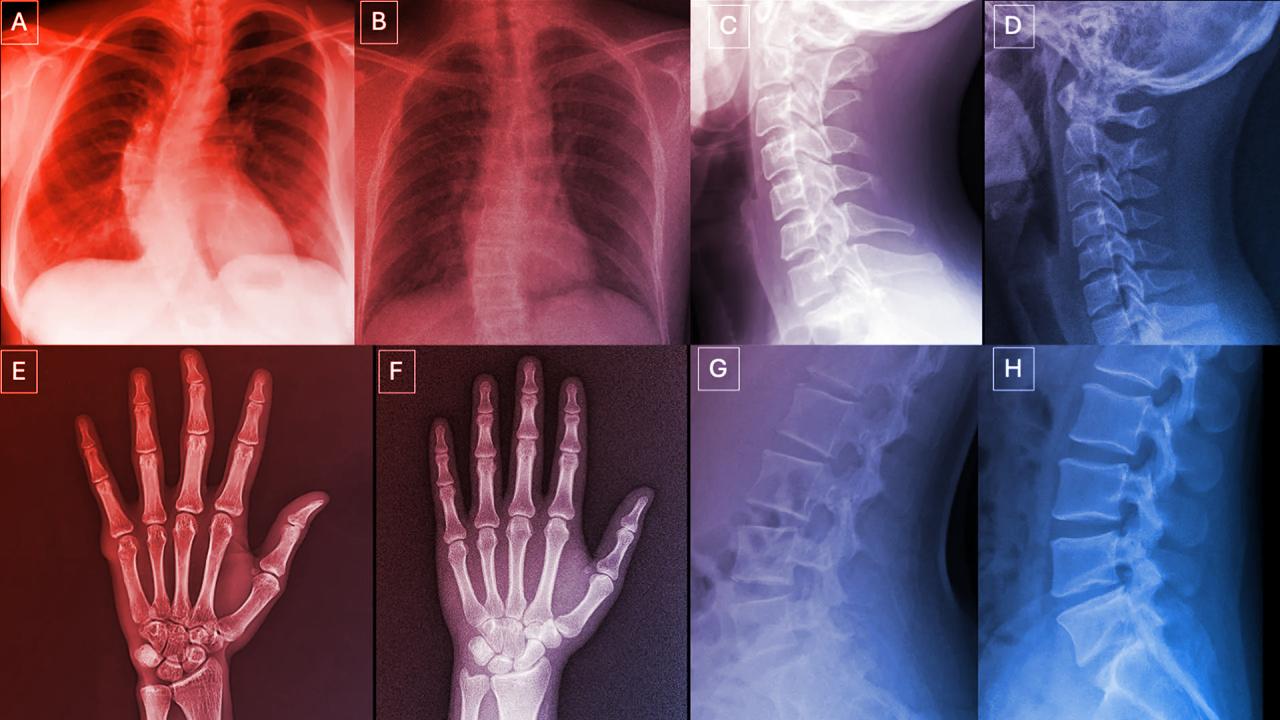

Egy nemzetközi kutatás során 17 radiológus – köztük kezdők és negyven éve gyakorló szakemberek is – több száz röntgenképet vizsgált meg, amelyeknek fele valódi volt, a másik fele pedig MI által generált. A szakértelem meglepően kevéssé számított: amikor nem tudtak az MI-alkotta képekről, csak 41%-os pontossággal szűrték ki a hamisítványokat. Ha előre figyelmeztették őket a deepfake lehetőségére, akkor is csak 75%-os volt az átlagos felismerési arány.

Mindazonáltal a különböző eszközök – például a ChatGPT vagy a RoentGen generatív modellek – sem tudták hibátlanul leleplezni őket, és a legjobb MI-k sem teljesítettek 89%-nál jobban. A tapasztalt mozgásszervi radiológusok ugyan jobban szerepeltek, de az évek során szerzett rutin nem volt garancia a sikerre.

A kutatók felfigyeltek néhány árulkodó mintázatra. A deepfake röntgenképek gyakran túl tökéletesek: a csontok szokatlanul simák, a gerinc szokatlanul egyenes, a tüdőmezők egyformák, az erek mintázata túl szabályos, a törések pedig feltűnően letisztultak, csak egy oldalra korlátozódnak.